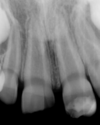

Horizontal bone loss with intact apex – diagnosis?

• Periodontitis chronica

• (chronic periodontitis).

• Treatment: Periodontal therapy

* Periodontitis chronica * (Chronic periodontitis) → Horizontal bone loss, apex normal